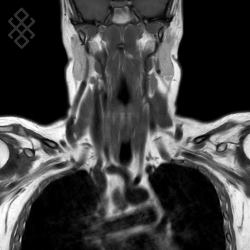

IRM du Rachis cervical

Vous entrez dans l'aimant, ouvert des 2 côtés, la tête la première et allongé sur le dos. Ensuite, pour recueillir le signal et construire les images, vous aurez la tête dans une antenne. Étant donné que cet examen est très bruyant, vous aurez à votre disposition des tampons auriculaires pour atténuer le bruit de la machine.

La durée moyenne de l'examen est de 25 min. Dans le cas d'une injection, le manipulateur en radiologie vous administrera le produit de contraste. Vous entendrez un bruit caractéristique à l'IRM faisant penser à un marteau piqueur.